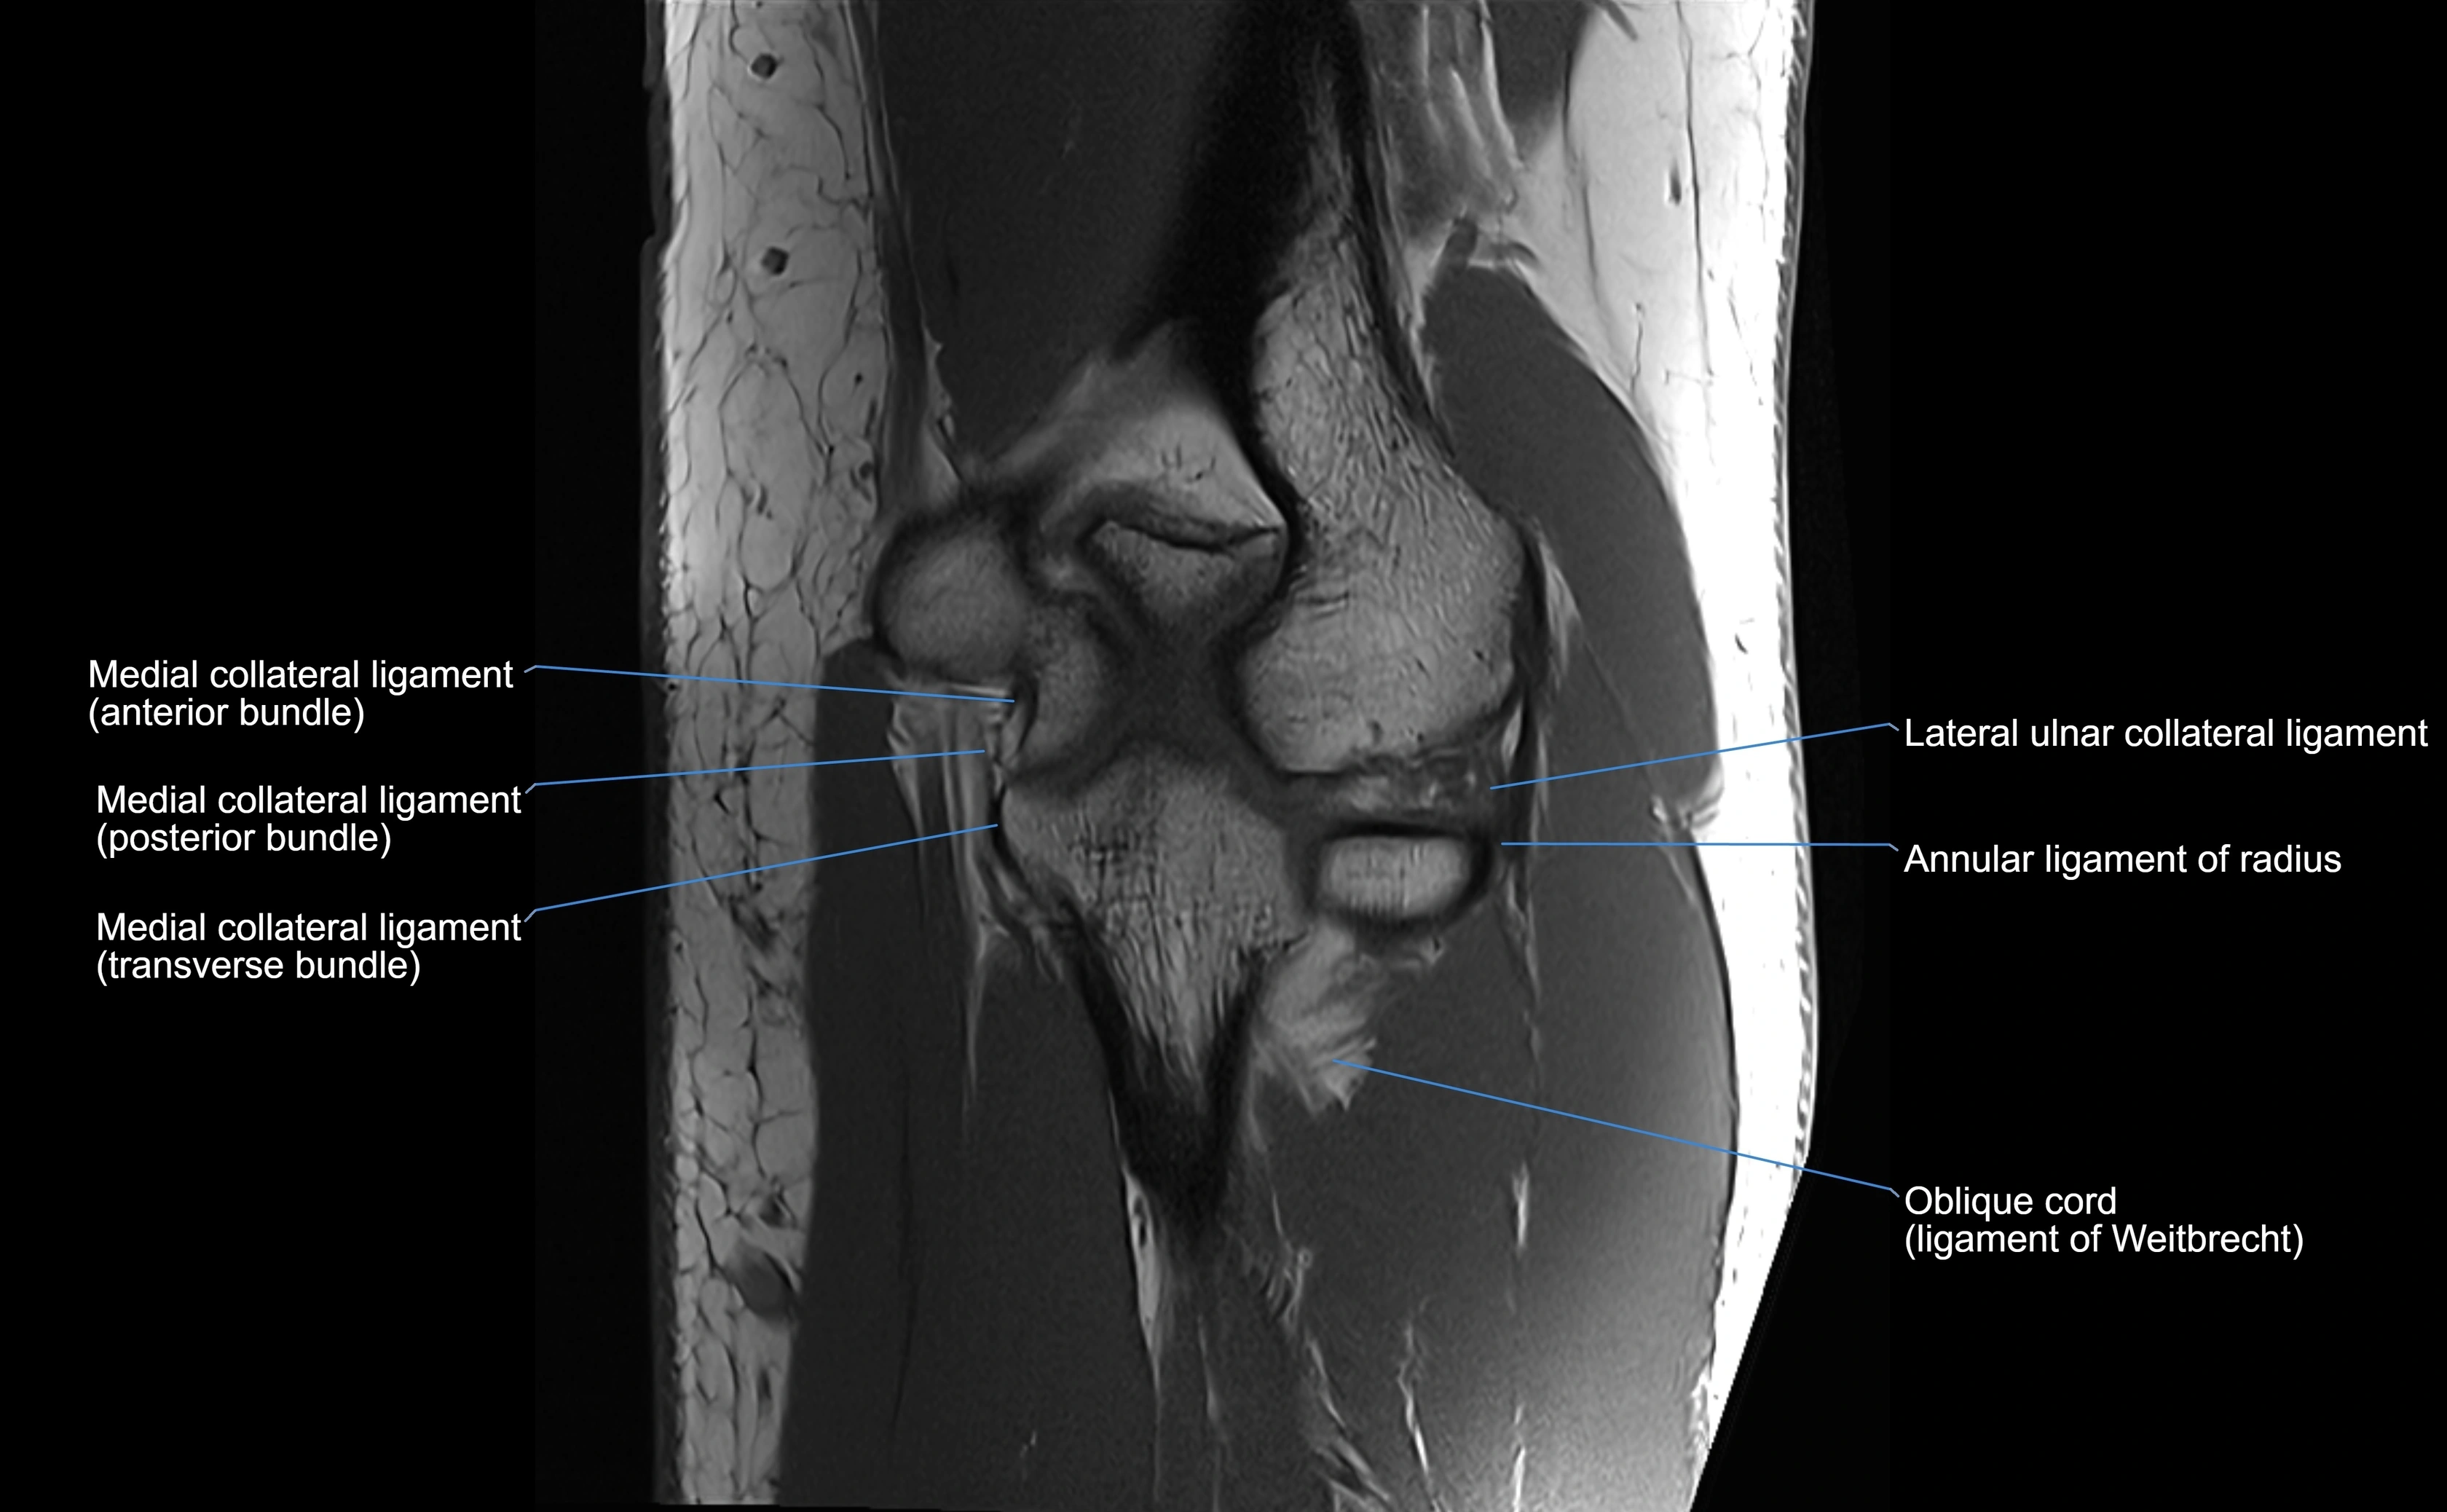

Annular ligament of radius

The annular ligament of the radius is a strong, circular band of fibers that encircles the head and neck of the radius, holding it securely against the radial notch of the ulna. It forms part of the proximal radioulnar joint, permitting smooth rotation of the radius during pronation and supination of the forearm.

The ligament acts like a collar or loop, maintaining radial head stability while allowing rotation. It is essential for forearm motion, elbow stability, and load transmission from the radius to the ulna and humerus.

Origin, Course, and Insertion

• Origin: Arises from the anterior margin of the radial notch of the ulna.

• Course: Forms a strong circular band that wraps around the radial head and neck, maintaining them within the radial notch.

• Insertion: Attaches to the posterior margin of the radial notch, completing a fibrous ring around the radial head.

• The inner surface of the ligament is lined with synovial membrane, allowing frictionless rotation.

MRI Appearance

T1-weighted images:

• Ligament: low signal intensity (dark), appearing as a continuous band around the radial head.

• Adjacent fat and marrow: bright, creating contrast with the ligament.

• Thickening or disruption indicates injury or fibrosis.

• Joint capsule and synovium seen as thin low-signal lines contiguous with ligament margins.